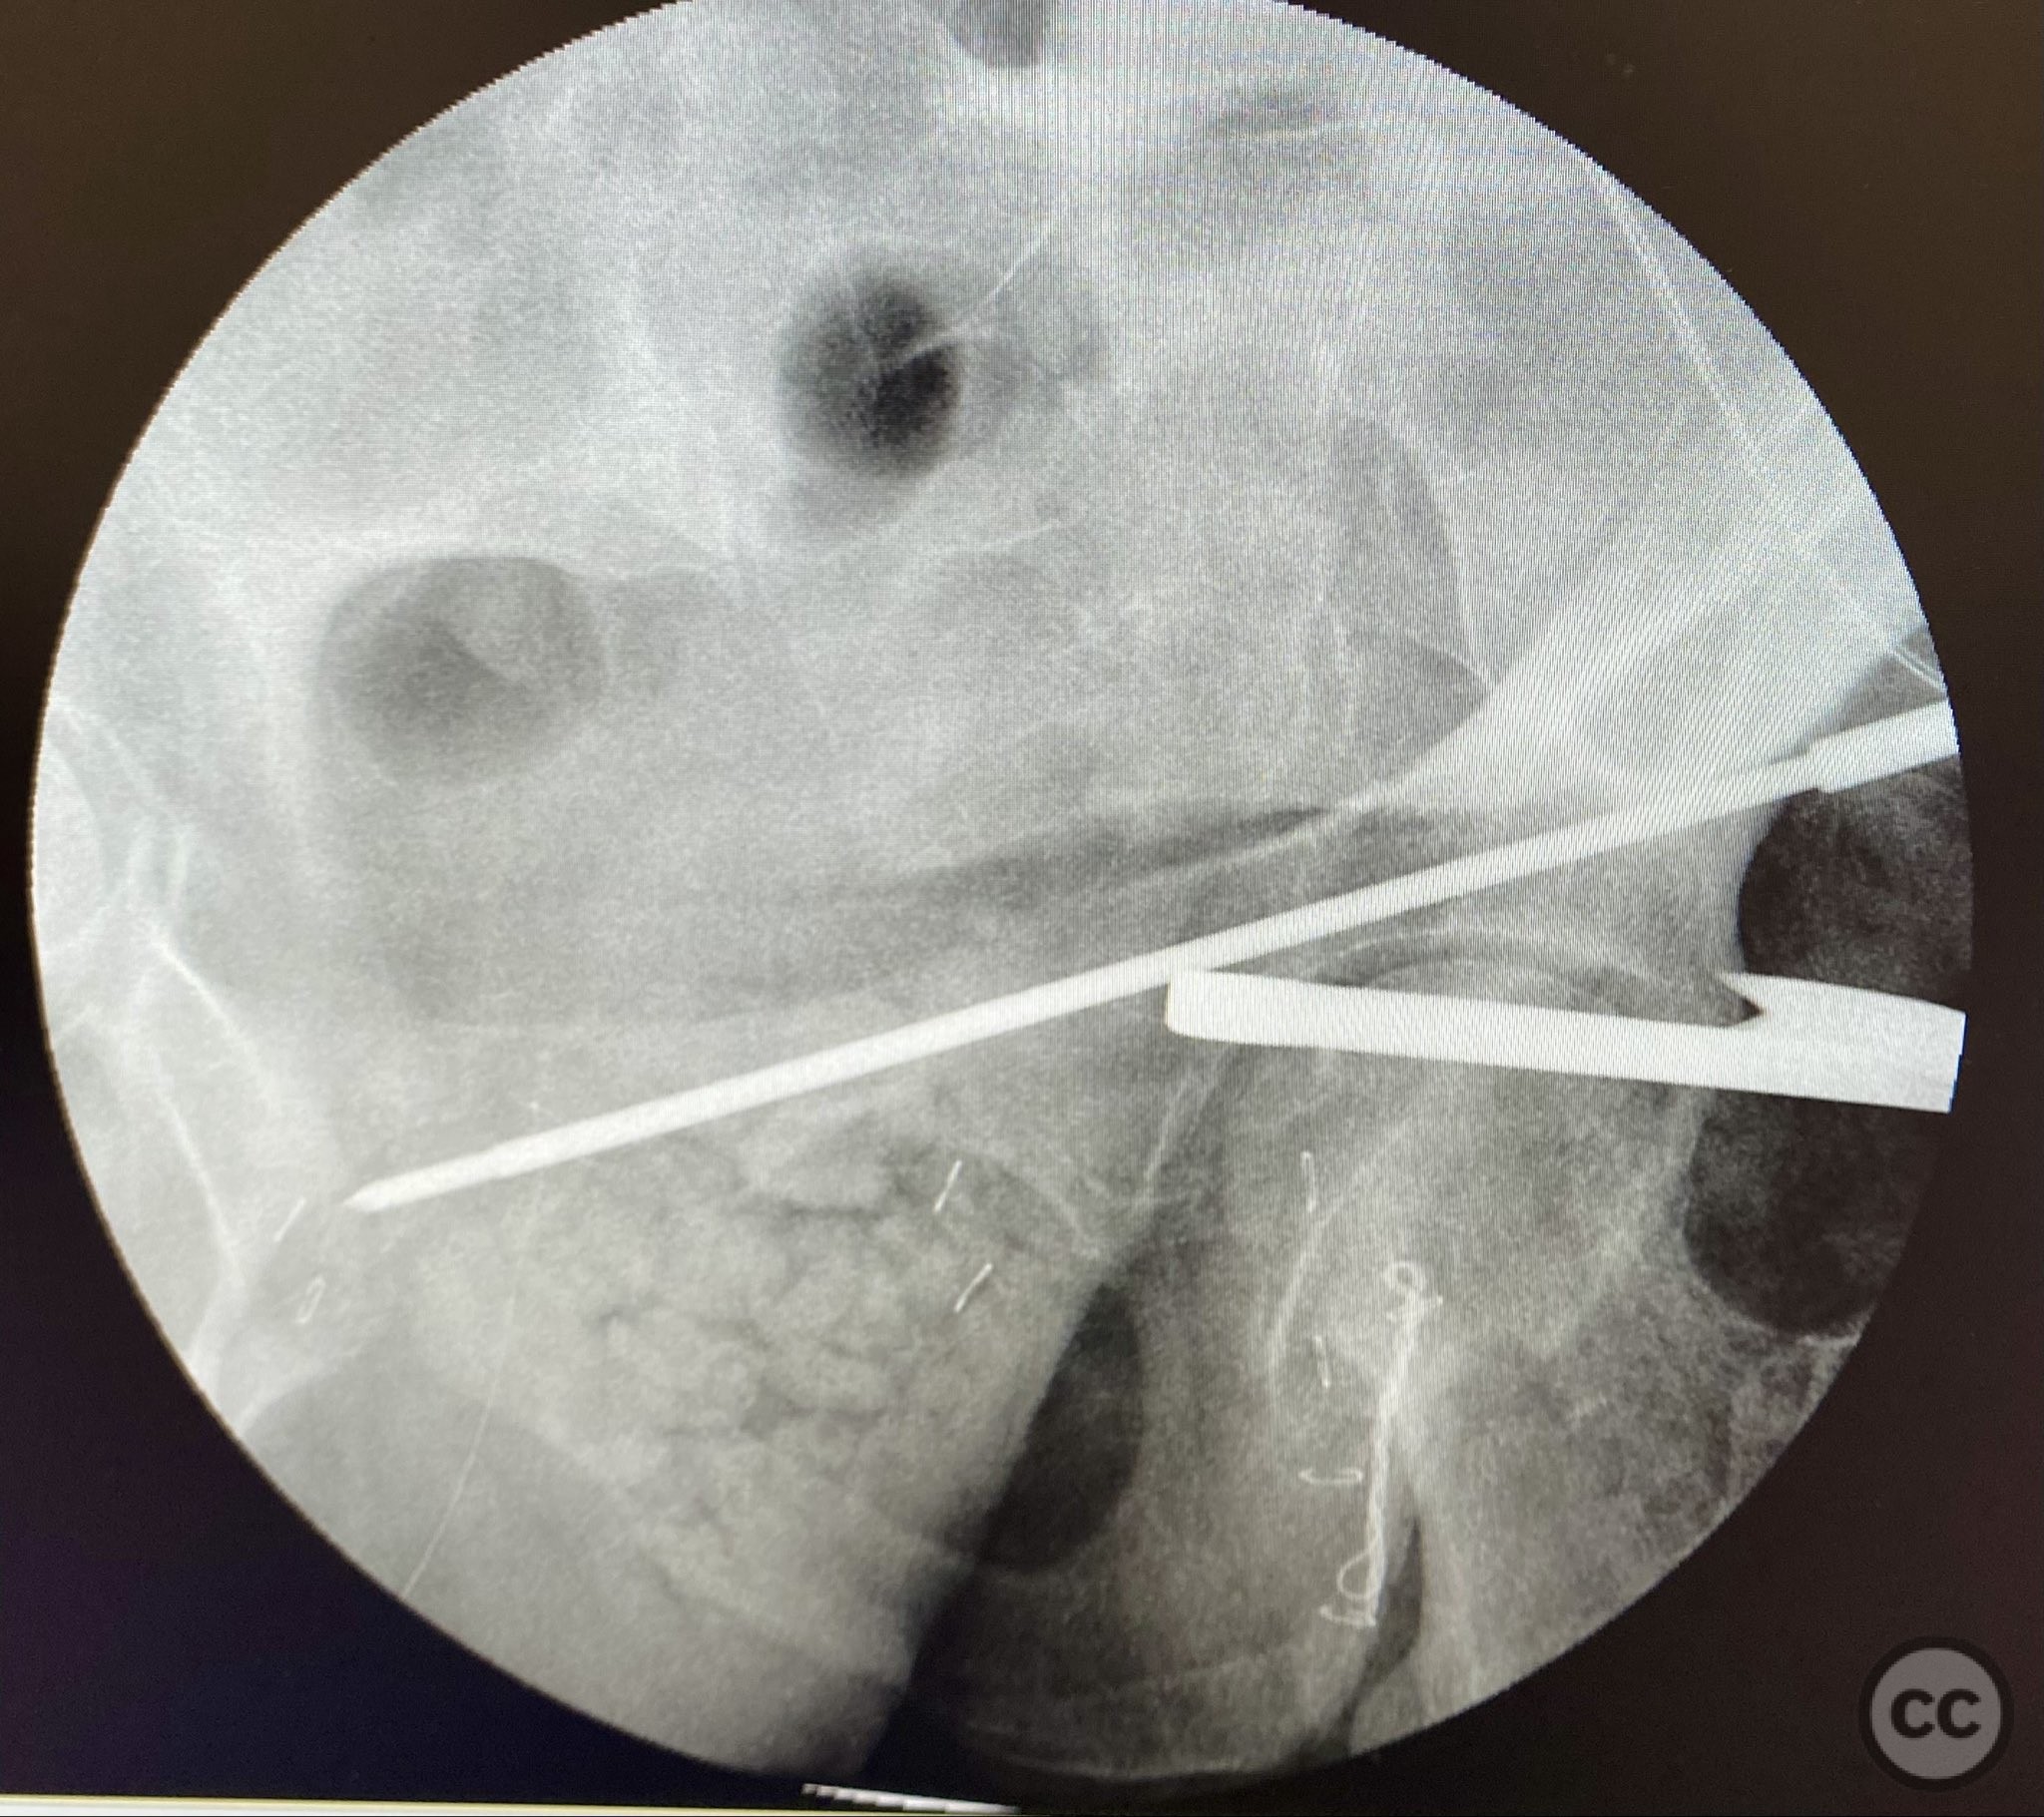

Operative remarks:

The transverse fracture was manipulated and temporarily stabilized using a reduction clamp applied across the fracture plane. Under biplanar fluoroscopic guidance, a cannulated cancellous lag screw was percutaneously inserted to achieve interfragmentary compression across the transverse component. The reduction clamp was then removed. Posterior wall fragments were anatomically reduced and stabilized with contoured buttress plates spanning both the posterior wall and providing additional stabilization to the transverse component. Postoperative CT confirmed satisfactory reduction and fixation of both acetabular columns and restoration of articular congruity.